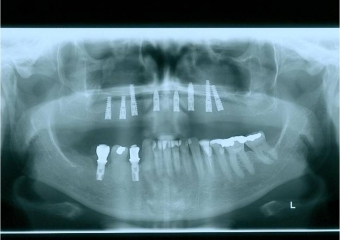

Raio x após instalação dos implantes superiores Cone Morse